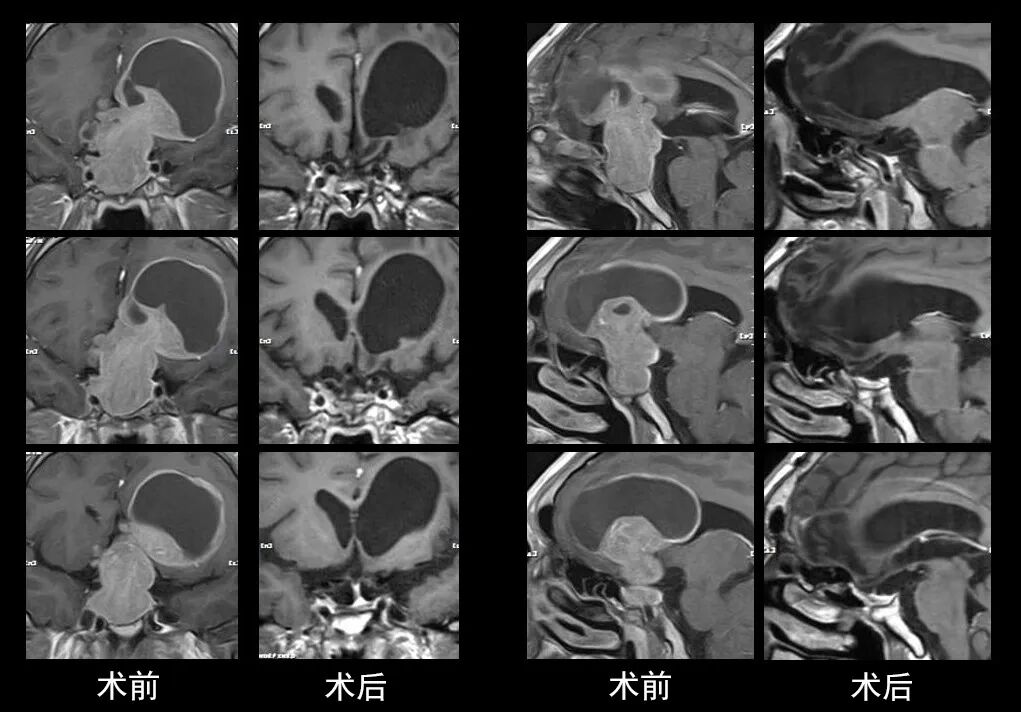

本研究中采用联合手术策略的代表性病例展示:

左右滑动查看更多

图片

case 1

case 2